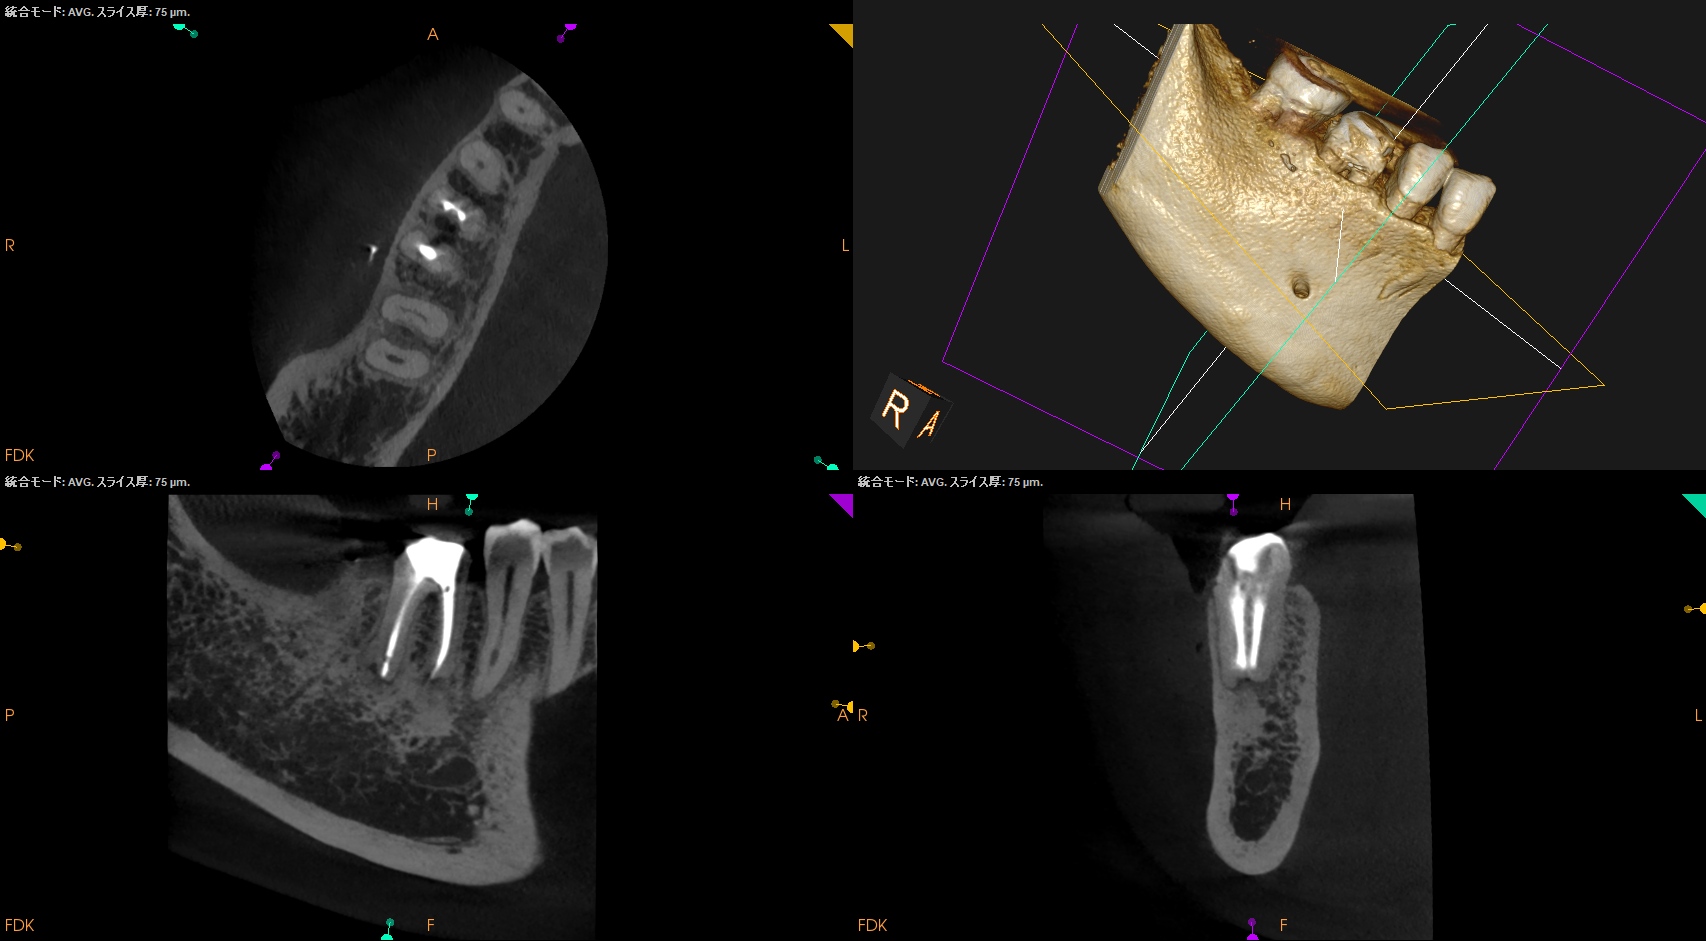

術後にPA, CBCTを撮影した。

MB

ML

D